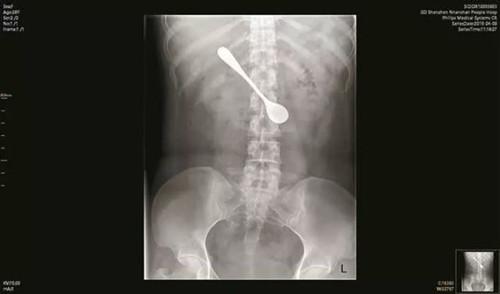

就在今年的清明前,一女子被鱼刺卡住喉咙。该怎么取出这根刺呢?这位女子顺手就拿起了身边的勺子,想把鱼刺掏出来。但是没想到勺子伸进喉咙时一不小心刺激了喉咙,一收缩,女子本能反应手劲一松,勺子掉进了胃里。

本来鱼刺并没有卡的很深,直接叫个人来就可以取出。但是这位女子的一顿“骚操作”直接把自己送进了手术室。(不幸中带有幸运,这么大的勺子没有造成更严重的后果)